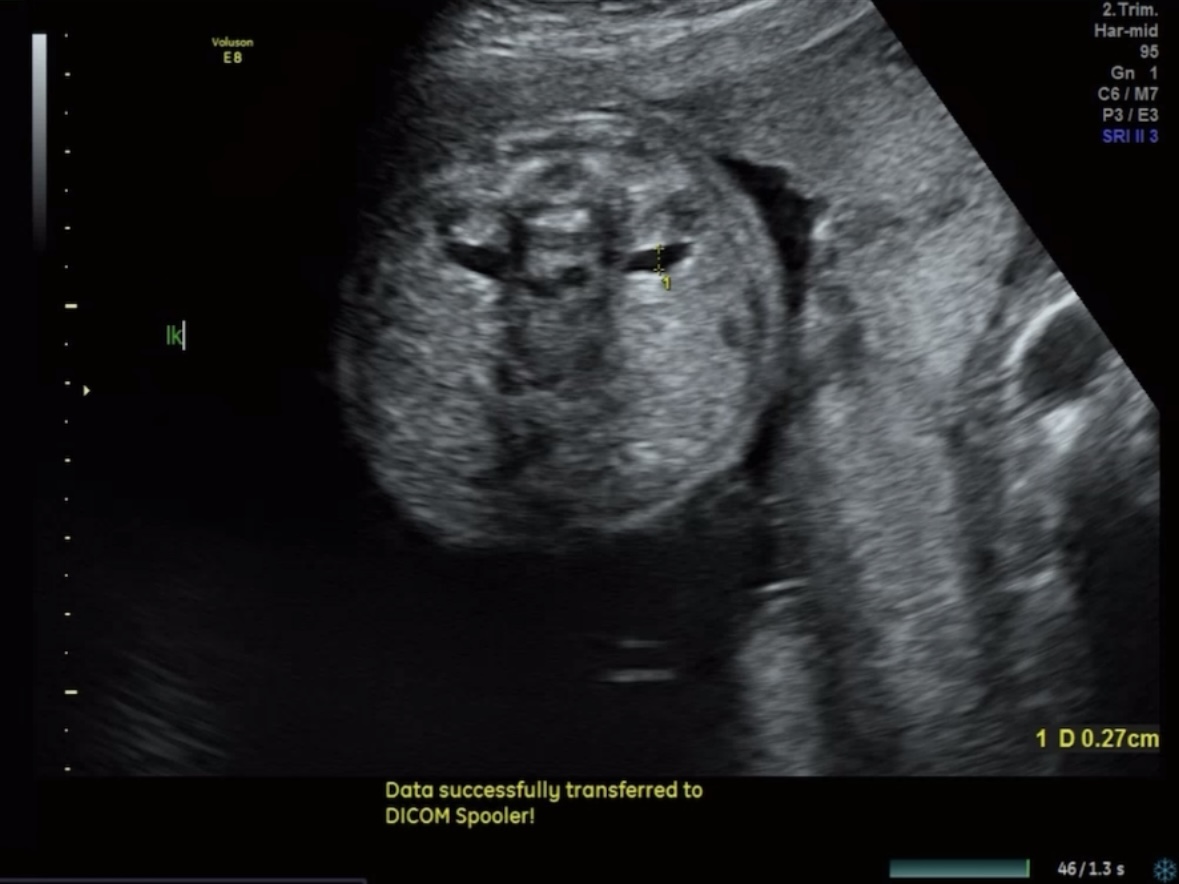

척추, 뇌

척추가 제대로 잘 닫혀있는지 확인한다. 잘 닫혀있음!

▒ 관련 초음파 용어

· Va(Ventricular Atrium): 대뇌 측뇌실(Atrium) 크기 측정(정상 범위: ≤10 mm)

· Vp: 대뇌 측뇌실의 뒤쪽(이상 소견 시 수두증 의심 가능)

· Cereb: 소뇌

· NF: 목덜미 두께(정상 범위: ≤6 mm, 21주 기준)

뇌도 정상적으로 발달했고 뇌실도 정상범위에 있었다.